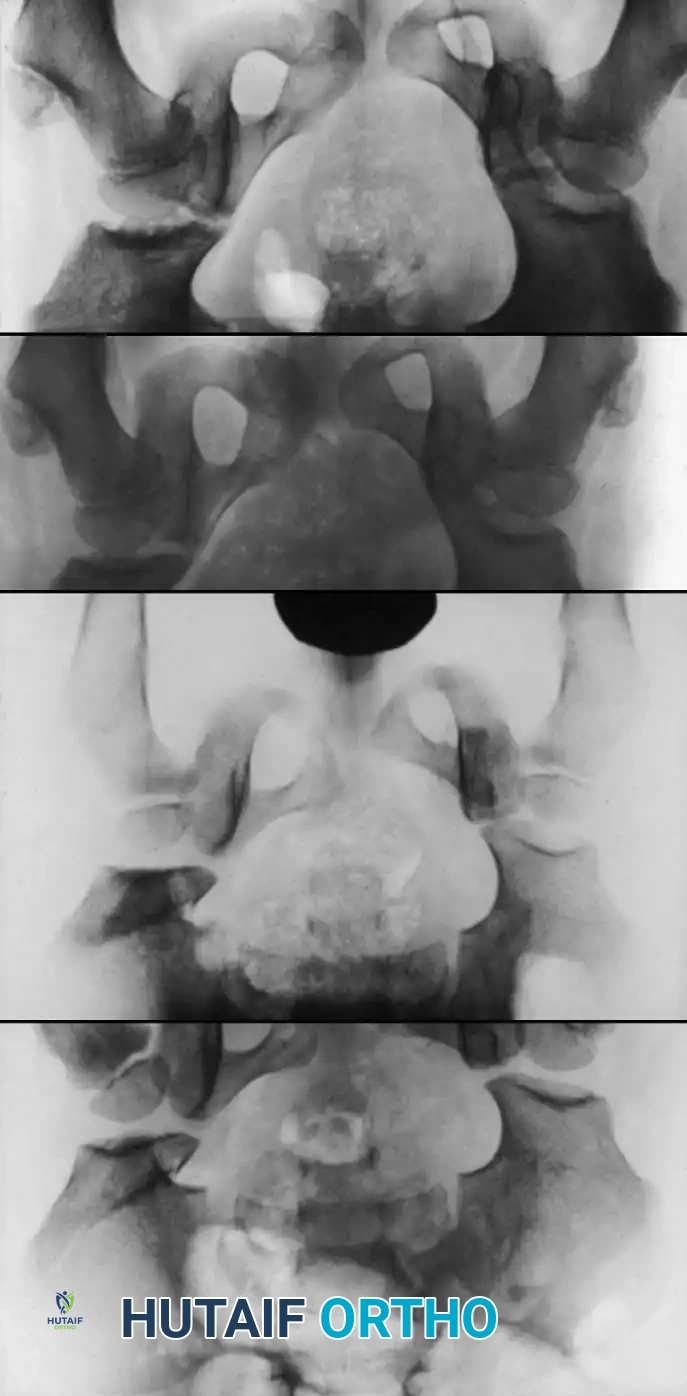

Fig. 1: Premature closure of the triradiate cartilage following severe pelvic and hip trauma, illustrating the profound impact of injury on the growing pediatric pelvis.

Fig. 2: Schematic representation of the hemipelvis and types of pediatric injuries, highlighting the vulnerability of the physis.

Fig. 4: Severe fracture-dislocation of the hip, demonstrating the high-energy nature of these injuries.

Fig. 5: Radiographic progression of a complex pediatric hip injury requiring extensive reconstruction.

Fig. 6: Long-term follow-up showing severe ankylosis and traumatic arthritis secondary to osteonecrosis.